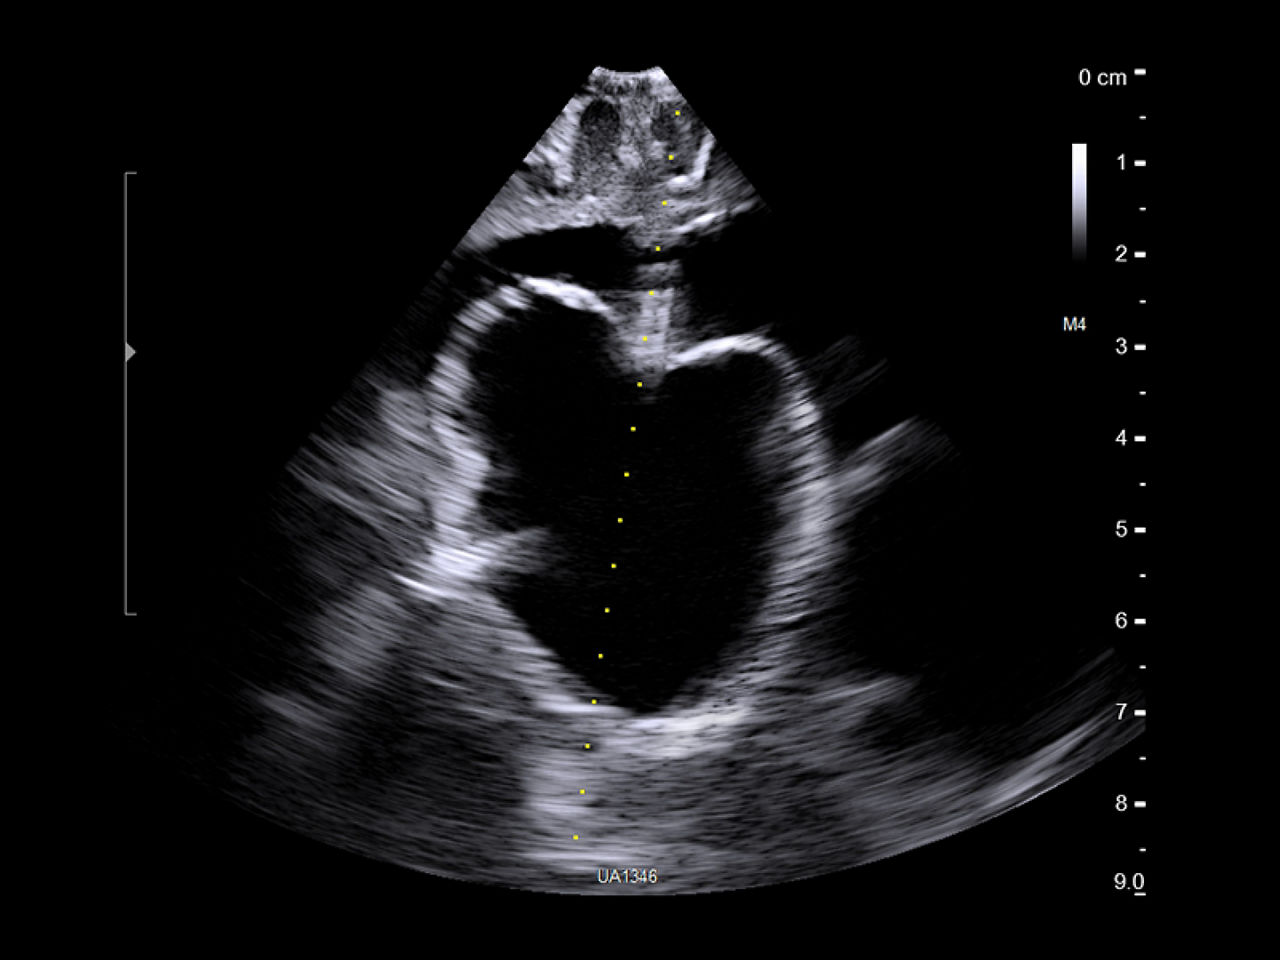

Intraoperative ultrasound solutions for neurosurgery and spine

Discover the power of real-time imaging with intraoperative ultrasound (iUS) for neurosurgery and spine. iUS provides neurosurgeons with real-time guidance to identify brain shifts, assess tumor resection, and avoid vital structures. Optimize outcomes with advanced imaging for high-grade gliomas, metastases, and complex spinal procedures.

Real-time active imaging for your neurosurgery procedures

Neuro-oncology

Use intraoperative ultrasound during surgery to assist in the identification of brain shift after pre-operative scans and determine extent of resection and assess for residual tumor.

Active imaging is real-time visual guidance for decision support

Real-time intraoperative imaging